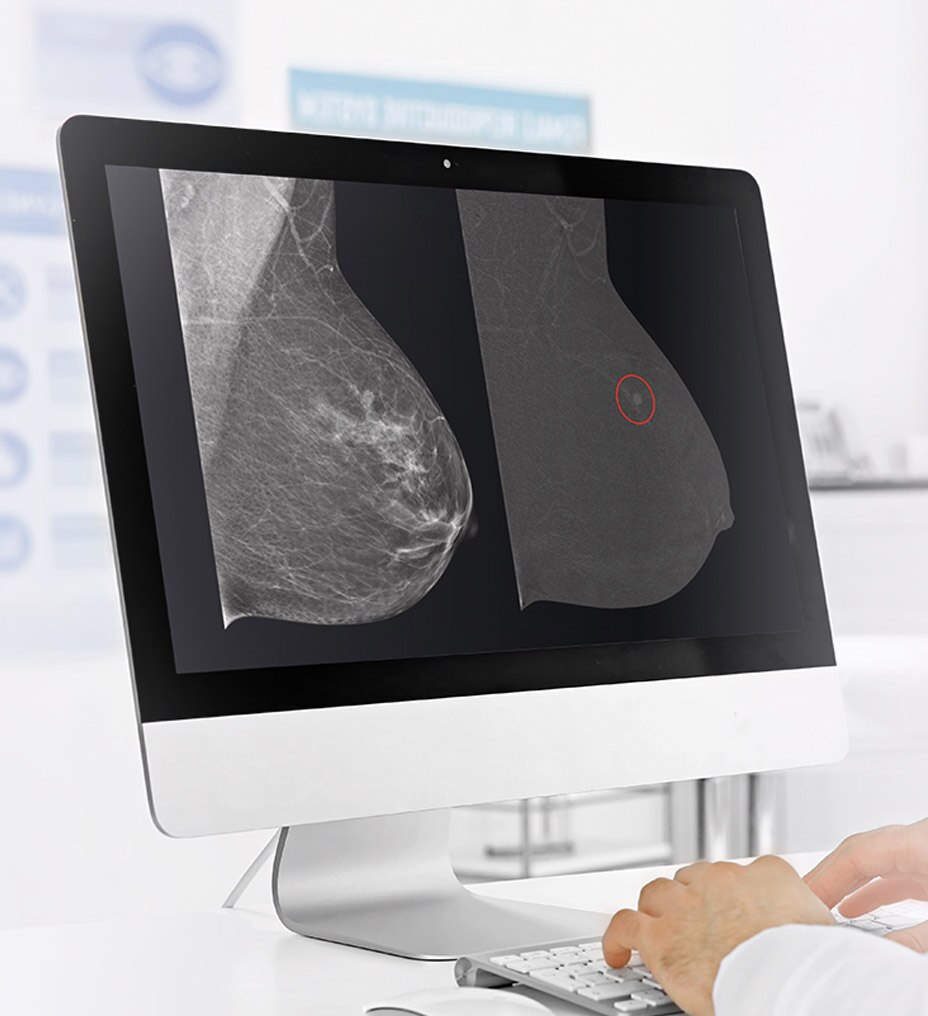

Daha net görüntüler daha kolay tanılar anlamına gelir ve derin öğrenme teknolojimiz AIR™ Recon DL ile olağanüstü kalitede görüntüleri daha hızlı elde edebilirsiniz. Çok çeşitli anatomiler için en net sonuçları sağlayarak MR görüntülerini görüntüleme biçiminizde devrim yaratır.

Ayrıca, göz yorgunluğunu azaltabilen okunması kolay, yüksek kaliteli taramalarla elde ettiğiniz görüntülerin kalitesinden daha emin olarak oluşturulan raporların daha iyi bir genel deneyime sahip olmasını sağlayabilirsiniz.